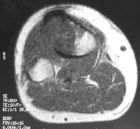

23 year old man with right knee pain, swelling for the past two months

Zoom image: Radiological image Radiological image.

Zoom image: Cell stain Cell stain.